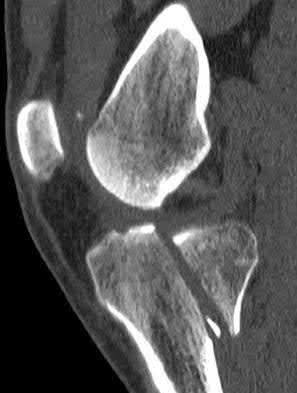

1. # A 32-year-old male sustains the injury shown in Figure A and undergoes treatment as shown in Figure B. Following placement of this implant, what is the best technique to confirm it is not too proud proximally?

The safe zone for tibial nail placement as seen on radiographs is just medial to the lateral tibial spine on the anteroposterior radiograph and immediately adjacent and anterior to the articular surface as visualized on the lateral radiograph.

Tornetta et al specifically located the safe zone for nail entry in a study using fresh frozen cadaver knees. The authors found that the safe zone for nail placement is located 9.1+/-5 millimeters lateral to the midline of the plateau and three millimeters lateral to the center of the tibial tubercle. The width of the safe zone averaged 22.9 millimeters and was as narrow as 12.6 millimeters.

The starting point of the of the nail can be best viewed on the lateral knee radiograph, an example of which is shown in Illustration A. Illustration B shows the "sweet spot" for nail insertion as defined by Tornetta.